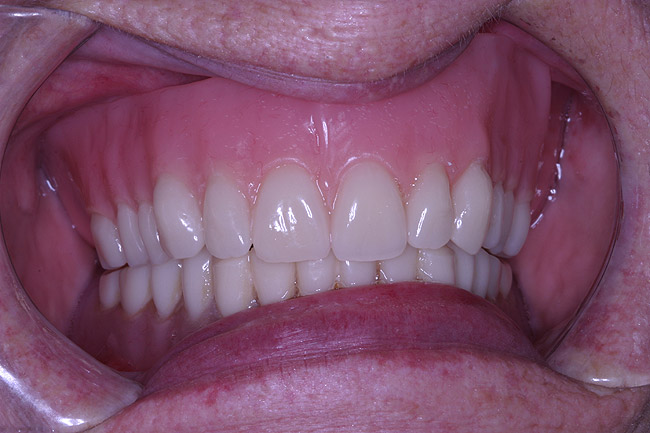

Figure 15  Final case, postoperative.

Figure 15

The laboratory then fabricated a light-cured, stabilized base plate on which anterior and posterior teeth were set using the silicone putty mold made previously and waxed up to final contour and delivered to the office. The upper denture was tried in and a visual examination was performed to certify function, esthetics, phonetics, and patient/clinician satisfaction (Figure 14). The denture was sent back to the laboratory for final processing with the Ivocap Denture System (Ivoclar Vivadent North America, Amherst, NY). The prosthesis was trimmed and polished to high luster to prepare for final insertion (Figure 15). Additionally, Massachusetts requires denture labeling with a patient identifier (wearer's name, driver's license number, or Social Security Number, etc) for forensic purposes, and this was exacted according to state law.28